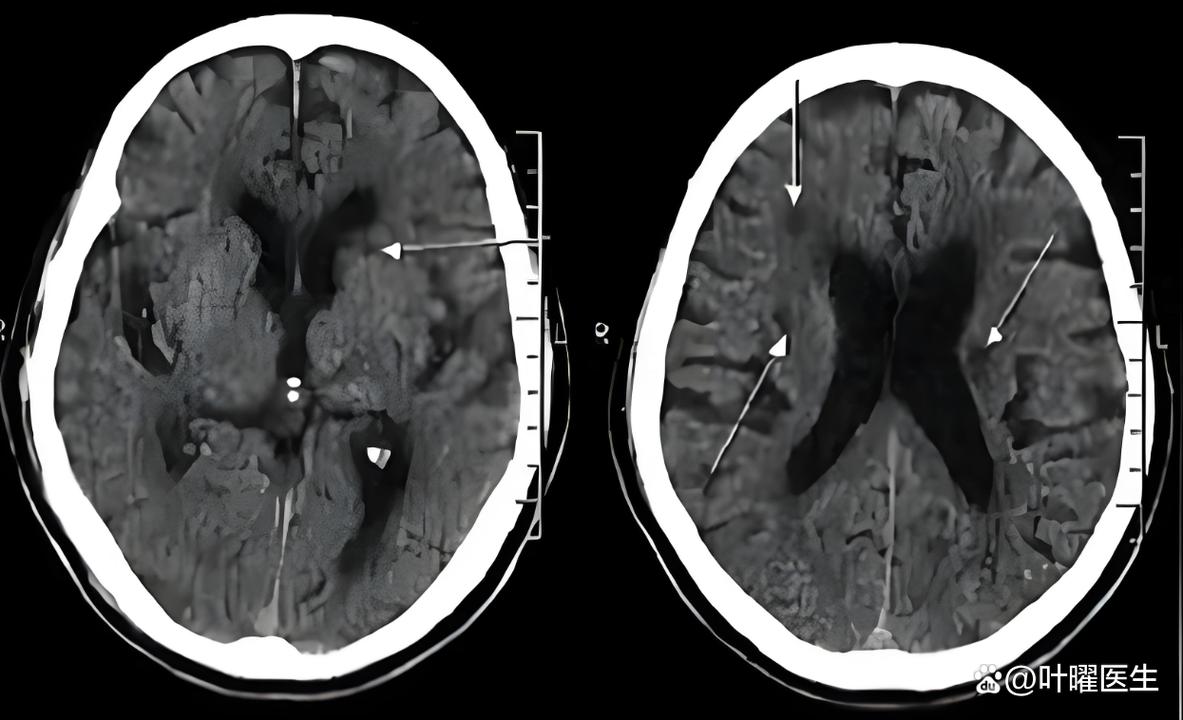

腔梗:

(图片来源网络,侵删)- 这是核心诊断。“腔隙性脑梗塞”的简称。

- 简单理解:可以把它想象成大脑里非常微小的“小中风”或“小梗塞”。

- 形成原因:我们的大脑里有非常细小的血管,叫做“穿通动脉”,这些血管为大脑深部的一些重要结构(如基底节、丘脑、脑干等)供血,当这些小血管因为各种原因(比如堵塞、变性)发生堵塞时,它所供应的那一小块脑组织就会因为缺血而坏死,形成一个微小的“洞”或“腔隙”,这个坏死区域就叫做“腔隙性脑梗塞”。

- 大小:通常病灶非常小,直径一般在1.5-3毫米左右,所以报告描述为“少许”,说明数量不多,且体积很小。